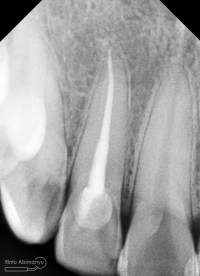

Ini foto ronsen setelah selesai perawatan..

Terus bagaimana dengan foto klinis setelah penambalan ?? Nah ini dia, biasanya daerah palatal sering tidak diekspos bila dilakukan restorasi, karena tidak terlihat langsung terkadang penambalannya pun sekedar “yang penting ketutup” hehehe

Nah saya mencoba untuk tidak meng-anak tirikan tambalan palatal, ini dia hasilnya…

So… “Esthetic on palatal, why not ?” 😛